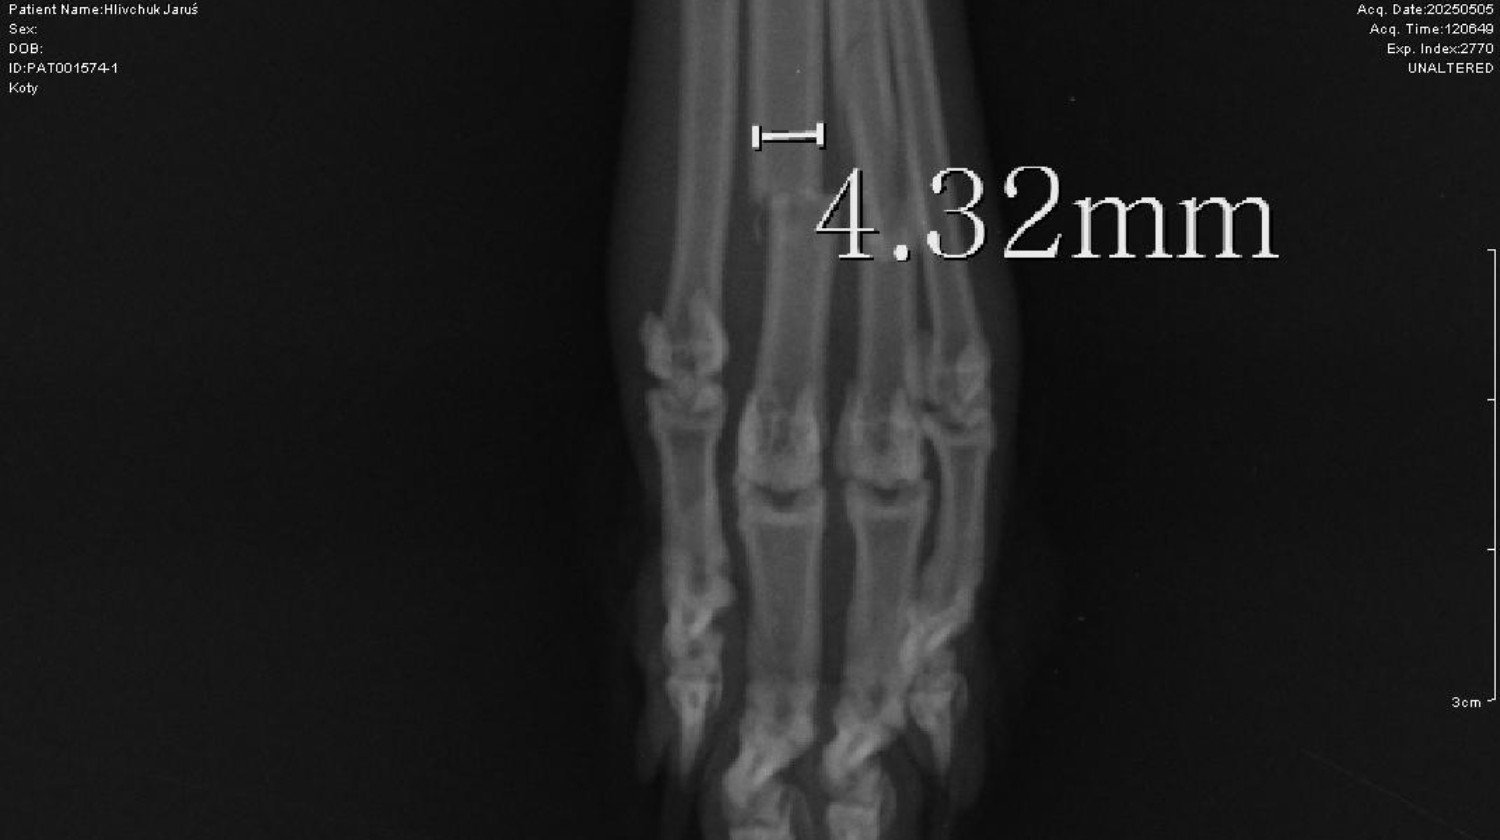

Po konsultacji z lekarzem i badaniu RTG okazało się, że Jaruś ma złamane dwa palce tylnej lewej łapki, a kości na siebie nachodzą. Potrzebna jest operacja ortopedyczna z wstawieniem gwoździ, która odbędzie się w specjalistycznej klinice ortopedycznej w Lublinie. Leczenie potrwa około dwóch miesięcy, z kolejną operacją w celu usunięcia gwoździ.

Profil jest obecnie w trakcie weryfikacji, co może potrwać kilka dni, ale zbiórkę zdecydowałam się rozpocząć wcześniej ze względu na pilność sytuacji. W razie potrzeby mogę okazać wszystkie dokumenty potwierdzające leczenie, faktury, zdjęcia RTG i przebieg terapii.